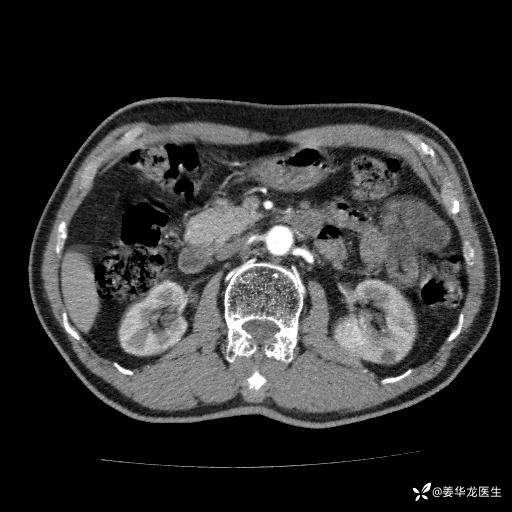

左肾中心型肾门部肿瘤39mm×34mm×36mm,右肾GFR25ml/min,部分切还是全切?

患者75岁老年男性,体重50kg,无高血压、肾病、糖尿病等基础病,检查发现左肾中心型肾门部肿瘤,右肾GFR只有25ml,无肉眼血尿,无镜下血尿。入院验血常规检查均正常,包括肾功能,肌酐102.7umol/L.

二、左肾肿瘤与左肾集合系、左肾动静脉关系密切,左肾部分切除术可行吗?成功率有多大?成功部分切后,肾功能还有多少?